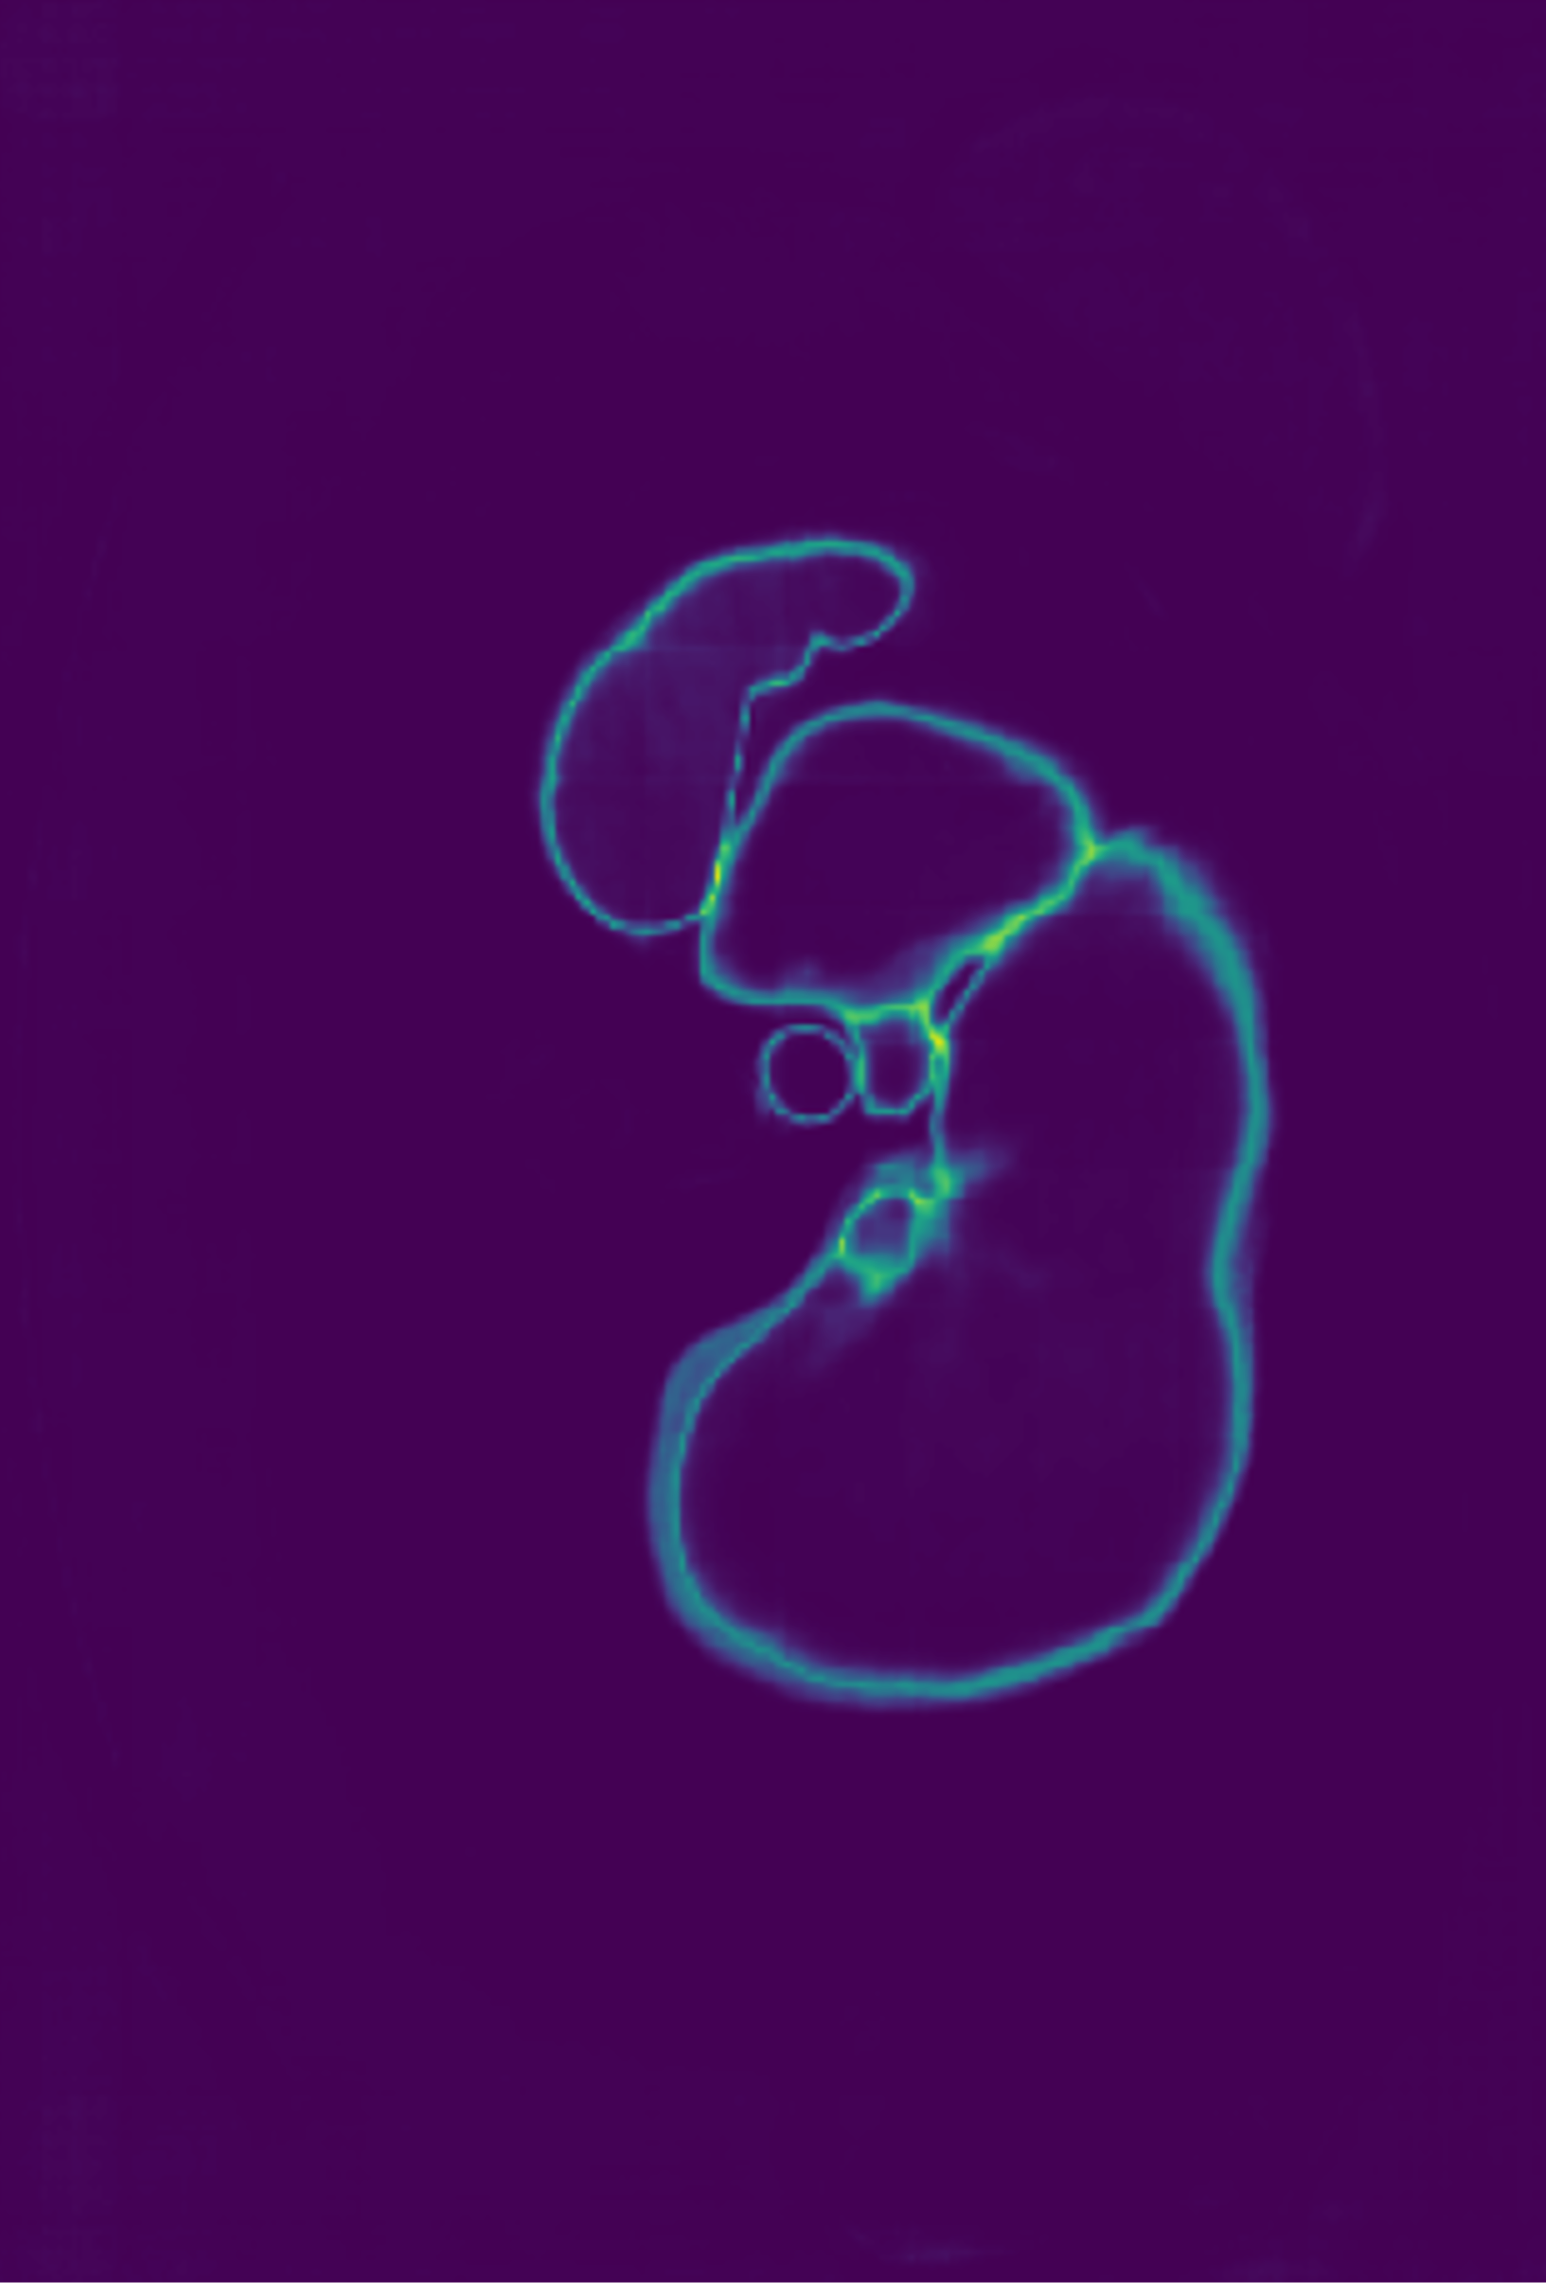

3.3 Entropy Test-Time Adaptation (ETTA)

A common practice in medical imaging to addresses the labels distribution-shift is to employ Test-Time Adaptation (TTA) by fine-tuning model parameters at test time using only test data without ground-truth [33]. To mitigate the impact of any residual label noise at UKBOB, we introduce Entropy Test-Time Adaptation (ETTA). ETTA refines the model’s predictions on test samples by fine-tuning the batch normalization parameters using the test data itself, guided by minimizing the prediction entropy. Given a test sample , we first obtain the network’s initial prediction , where is the softmax probability over classes at each of the voxels in the sample. Here, represents the segmentation network parameterized by . We define the entropy loss over the predicted probabilities:

We update only the batch normalization parameters while keeping the other network parameters frozen (see pipeline in Figure 4). The adaptation process involves minimizing the entropy loss with respect to :

This process adapts the model to the test sample by encouraging confident (low-entropy) predictions, thereby refining the segmentation output. The adaptation is efficient as it involves updating a small subset of parameters and can be performed online during inference. ETTA leverages the entropy of the network’s predictions (Figure 5) to guide the adaptation, improving robustness to domain shifts and label noise.